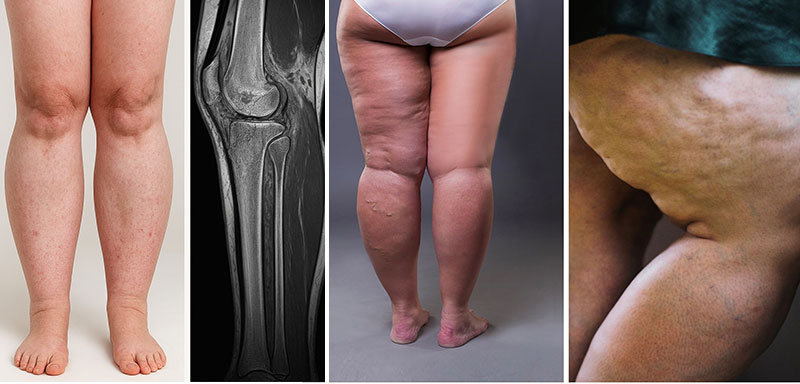

Linfedema o lipedema son términos ampliamente utilizados en el campo médico y estético pero a nivel general plantea dudas, existiendo un gran desconocimiento sobre cada uno: “Linfedema se da cuando existe una acumulación anormal de líquido proveniente de la linfa (rico en proteínas) en tejido subcutáneo, ya sea por un fallo o bloqueo en el sistema linfático. Por lo general se manifiesta con una hinchazón persistente (unilateral o asimétrica) o con una sensación de pesadez y endurecimiento progresivo de la piel, o en fases ya másavanzadas, cambios cutáneos como la fibrosis", nos comenta el Dr. Eskandari, director de las clínicas Golden Estética en Madrid (Calle Garcilaso, 7) y Viena.

A diferencia del lipedema, que es simétrico, doloroso a la palpación y afecta casi siempre a ambas piernas, el linfedema presenta un signo clínico característico: el signo de Stemmer positivo, que indica dificultad para levantar la piel en la base de los dedos. La hinchazón o celulitis por grasa localizada suele ser blanda, reversible con el reposo y no presenta la misma evolución ni las alteraciones del drenaje linfático. En casos dudosos, se apoya el diagnóstico con pruebas como la linfogammagrafía, el linfoscintigrama o la linfografía con ICG.

Con el linfedema conviene estar atentos, ya que de no tratarse adecuadamente, podría generar complicaciones importantes de salud: “Por ejemplo, infecciones recurrentes como celulitis o erisipela, dolor crónico y limitación funcional que reduce la capacidad de movimiento, cambios cutáneos progresivos incluyendo fibrosis y engrosamiento de la piel, ansiedad, depresión, alteración de la imagen corporal o en casos avanzados, úlceras o problemas dermatológicos severos, por ello se considera una enfermedad crónica que afecta la salud física y emocional, no sólo la apariencia”, matiza el Dr. Eskandari.